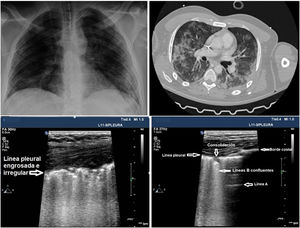

Los patrones de aireación de cada región pulmonar son (fig. 2):

- •

Patrón A: patrón típico de aireación normal. Línea pleural con deslizamiento conservado, presencia de líneas A y ≤ 2 líneas B bien espaciadas (fig. 2A y B).

Patrón B1: presencia de más de dos líneas B bien espaciadas, difusas en las distintas áreas del tórax, denominadas septal rockets (fig. 2C).

Patrón B2: líneas B confluentes separadas entre ellas por ≤ 3 mm (ground-glass rockets) debido a pérdida más severa de pulmón aireado (fig. 2D).

Patrón C: consolidación pulmonar, que sugiere pérdida importante de pulmón aireado por acúmulo de líquido y/o células en los alveolos. La consolidación puede detectarse en cualquier punto del hemitórax, pero la aplicación del transductor en el punto PLAPS detecta el 95% de los casos (fig. 2E y F).

Patrones de aireación pulmonar. A) Patrón típico de aireación normal (perfil A en el protocolo BLUE) mostrando imagen en 2D. B) Patrón A en modo M. C) Patrón B1. D) Patrón B2. E) Consolidación pulmonar (perfil C en el protocolo BLUE), mostrando signo del borde irregular o shred sign. F) Broncograma aéreo. A, B, C, D y E: estudio con sonda lineal; F: sonda convex.

En el caso de los pacientes con COVID-19 los hallazgos característicos dependen de la fase evolutiva de la enfermedad. Las primeras manifestaciones en el UP están representadas por una distribución irregular de líneas B focales y posteriormente confluentes que se extienden a múltiples áreas de la superficie pulmonar. La evolución posterior está representada por la aparición de pequeñas consolidaciones subpleurales con línea pleural engrosada e irregular con áreas asociadas de pulmón blanco, presencia de áreas parcheadas de patrón A y áreas con anomalías sin presencia de grandes DP. La evolución será hacia un patrón de consolidación, especialmente en zonas declives, con o sin broncograma aéreo, y su extensión creciente en la superficie pulmonar indica progresión hacia la fase de IRA que puede requerir VM.